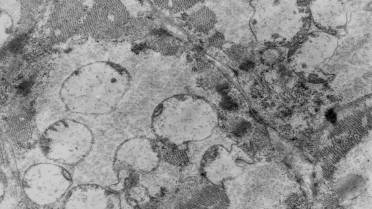

Типичным было образование массивных скоплений

органелл, состоящих из опустошенных гигантских митохондрий (рис. 2). Данные

изменения, на наш взгляд, свидетельствовали о вступлении клетки в

апоптотический процесс за счет инициации апоптоза по митохондриальному механизму

[3,4].

Рис. 2. Группы гигантских опустошенных митохондрий в

саркоплазме соседних кардиомиоцитов правого предсердия крысы на 14-е сутки формирования

экспериментального психоза. Ув.: ×14000.